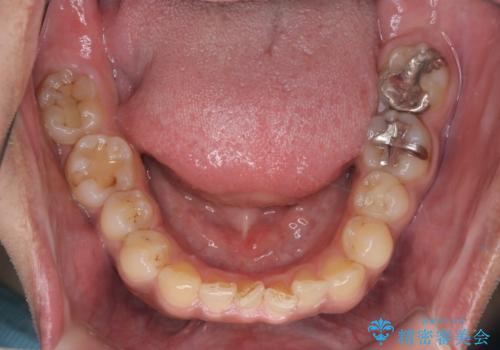

【モニター】インビザライン 前歯の捻れを治したい

- 30代男性

- 矯正装置

- インビザライン

- 治療計画

- 上下の前歯のがたつきを主訴に来院されました。インビザラインで治療可能と判断致しましたので、IPR(歯と歯の間を削る処置)と歯列弓拡大をして

がたつきをとる治療計画を立てました。

マウスピースをしっかり使用していただいたことで、主訴である前歯のがたつきも改善され

リファイメントも1回のみで治療を終了することが出来ました。